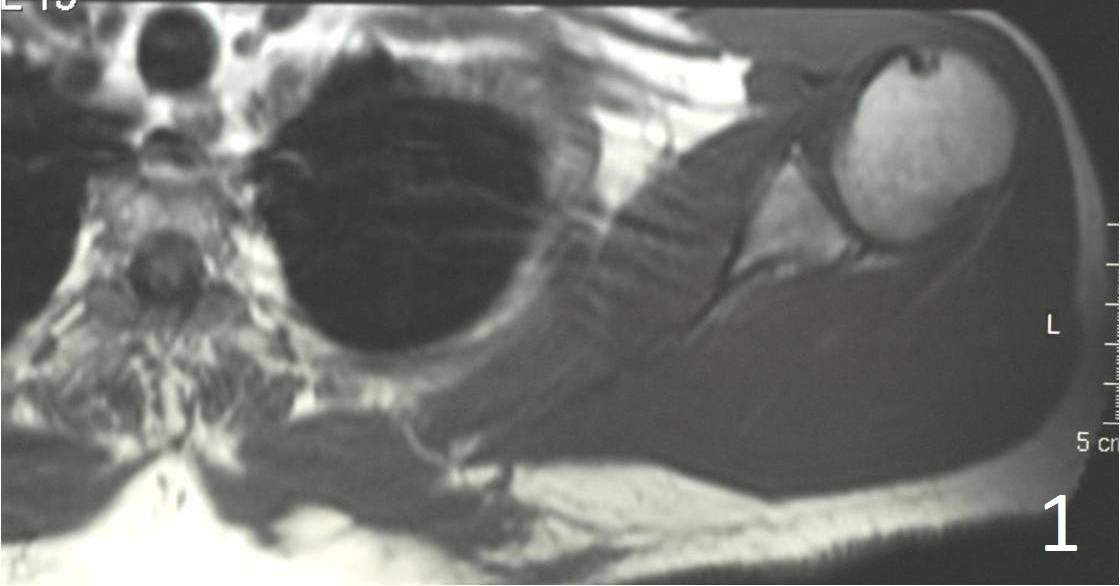

Large mass with heterogeneous signal intensity (Fig. 1, 2)

Strong enhancement post gadolinium (suggestive of malignant process)

Areas of necrosis and hemorrhage

Usually it is very difficult to detect any fat within the mass on an MRI

Fig. 1, 2 Axial MRI of shoulder shows a lesion in the subcutaneous tissue along the postermedial border of the scapula.